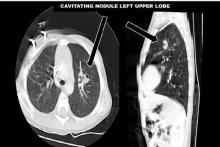

The video describes a VATS segmentectomy for a left upper lobe cavitating nodule in a 22-month-old child. The child was waiting for a bone marrow transplant, following failed chemotherapy for chronic myeloid leukemia. After non-invasive methods of obtaining a diagnosis failed, the child was referred for surgical biopsy. In view of the central proximity of the nodule to the segmental bronchus, a VATS (apicoposterior and anterior) segmentectomy was performed.